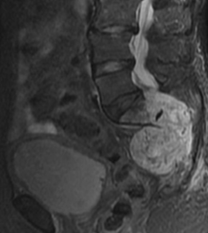

Renal oncocytoma with the characteristic central stellate scar of the neoplasm (Courtesy Dr. V. Penopoulos)